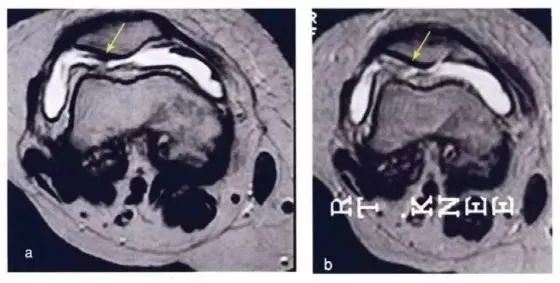

研究结果:关节内注射骨髓间充质干细胞6个月后,疼痛、功能状态和步行距离均提高。6名治疗组中3名患者在治疗前后的MRI比较可以看出,该治疗对于改善软骨厚度,修复组织延伸超过软骨下骨,以及减少软骨下骨的水肿是非常显著的

下图a示意治疗前软骨,b为治疗后6个月软骨,箭头所示为软骨修复位置。